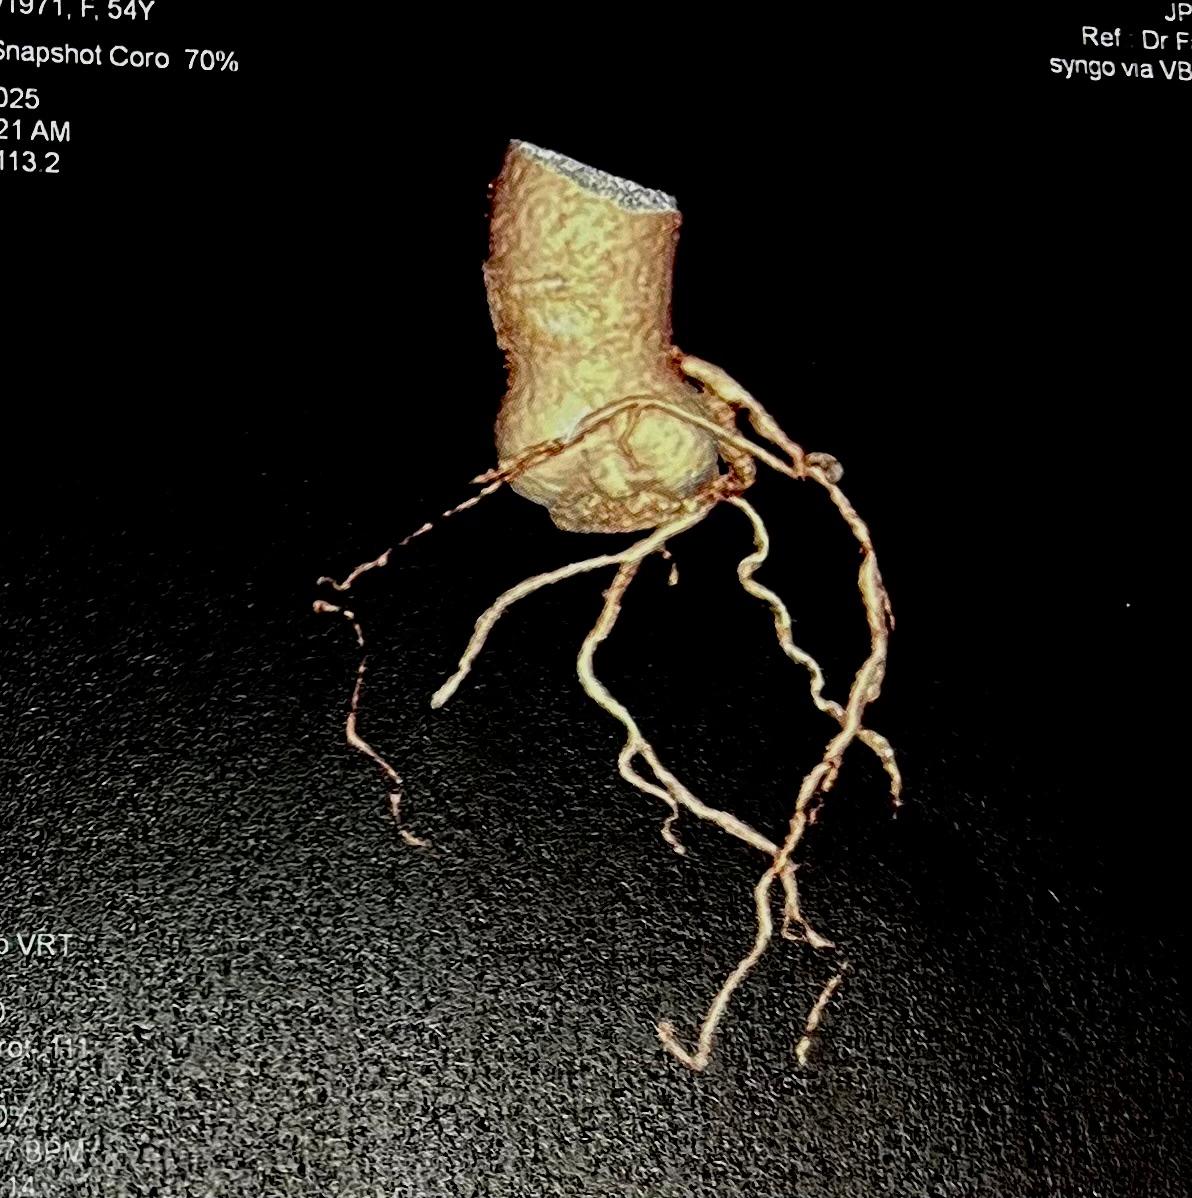

The initial angiogram on July 3rd, 2025, showed two-vessel coronary artery disease, with diffuse atherosclerosis extending from the proximal to distal LAD and moderate stenosis of the OM2. The RCA was absent and appeared to be supplied by the D1 branch, which showed severe disease at the ostium and mid segment. A repeat angiogram showed drop of blood flow with TIMI 2 flow to the distal LAD and RCAterritories. Then we proceed to PCI to LAD and RCA.

An IVUS-guided PCI of the LAD and RCA was performed via right radial access. An EBU 3.5, 7 Fr guiding catheter engaged the left main, and a Sion Blue wire was advanced to the distal LAD for pre-dilatation with a 2.5 mm NC balloon. Wiring the anomalous RCA from the LAD was challenging due to a retroflexed ostium but was achieved using a reverse wire technique with adual-lumen (Sasuke) catheter and Sion Black wire. Difficulty crossing the mid RCA, likely due to dissection, required multiple wire exchanges before reaching the distal RCA. Lesion preparation used 2.0 mm and 1.5 mm NC balloons in the RCA. IVUS showed LAD diameters of 2.5mm distally with diffuse disease and < 40%plaque burden. A hybrid revascularization strategy was planned. Further preparation involved 3.0 mm and 2.0 mm balloons in the LAD and RCA. DCBs (2.0 ¡¿25 mm in distal LAD; 2.0 ¡¿ 20 mm in RCA) were applied for 60 seconds each. A Xience Sierra 3.0 ¡¿ 38 mm DES was deployed in the proximal–mid LAD,post-dilated with 3.0–3.5 mm NC balloons and optimized with a 4.0 mm POT. IVUS revealed a distal edge dissection, covered with an additional overlapping Xience Sierra 2.75 ¡¿ 23 mm DES. Final IVUS confirmed good stent expansion (MSA6 mm©÷), and angiography showed non–flow-limiting distal LAD dissection with TIMI 3 flow in both LAD and RCA.